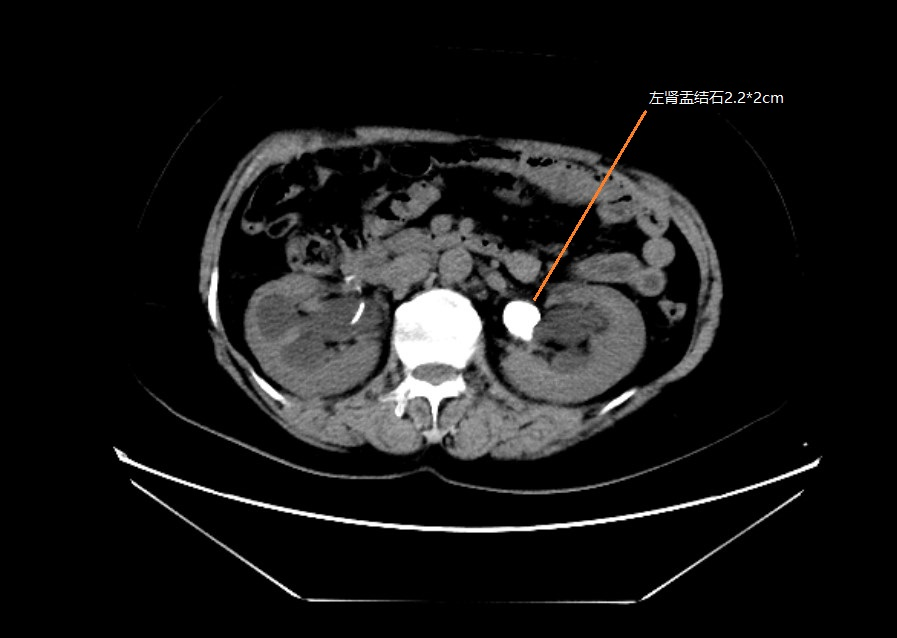

入院后患者存在尿路感染,按照診療指南給予抗生素治療1周,復(fù)查感染控制良好。經(jīng)多學(xué)科會(huì)診討論病情,認(rèn)為患者腎盂結(jié)石直徑大于2cm,積水明顯,腎下盞同時(shí)存在結(jié)石1*0.9cm,結(jié)石負(fù)荷量較大。首選經(jīng)皮腎鏡激光碎石取石術(shù),替代方案為:1。腹腔鏡腎盂切開取石術(shù),2。輸尿管軟鏡下激光碎石取石術(shù)?;颊呒凹覍倏紤]后同意行經(jīng)皮腎鏡激光碎石取石術(shù)。泌尿外科醫(yī)護(hù)團(tuán)隊(duì)積極完善術(shù)前準(zhǔn)備,排除手術(shù)禁忌后,在手術(shù)室麻醉護(hù)理及B超室等兄弟科室的輔助下成功行微通道經(jīng)皮腎鏡激光碎石取石術(shù)。

術(shù)中使用鈥激光粉碎腎盂大塊結(jié)石后將下盞結(jié)石轉(zhuǎn)移到腎盂擊碎并取出。